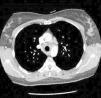

We performed a chest X-ray which displayed bilateral hilar lymphadenopathy (Fig. 2). To rule out a possible TB we performed a Mantoux test that was negative and serial urine auramines, which were also negative. We performed a high-resolution CT of the chest, which was compatible with grade I sarcoidosis (bilateral hilar and mediastinal lymphadenopathy) (Fig. 3). The transbronchial biopsy showed an inflammatory component in the bronchoalveolar lavage fluid and with a CD4/CD8 ratio of 5.26, with 80% of histiocytes, 15% lymphocytes and 5% neutrophils.